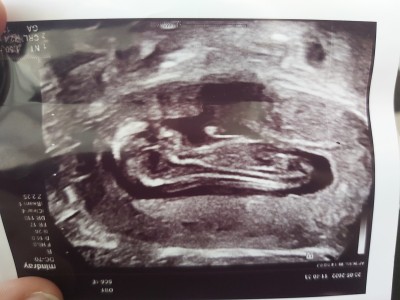

Sizce kızamı erkeğemi benziyor doktorumuz net birşey demedi merak ediyorum

Eğer doktor Emin degilse vardir bir Bildiği :ermm: demi 13 haftada cinsiyet tahmini değişken olabilir ve burada sadece resmi tahmin edin demeniz birde bunu tahmin edenide ne bileyim ki ya

12 haftalıkken tahmınde bulumuyolar 16 haftalıkda posızyonu acıksa net soyluyolar yanılma payıda oluyor canım

Bunarada canim kıza benziyor narin baksana kemik yapısına kızın olcak

erkek gibi canımm sen bakma alakasiz yorumlara insanlar buranin amacini kavriyamamislar :))

Ultrason kalitesi okadar kotu ki doktorda eminim ondan emin olamamistir :))